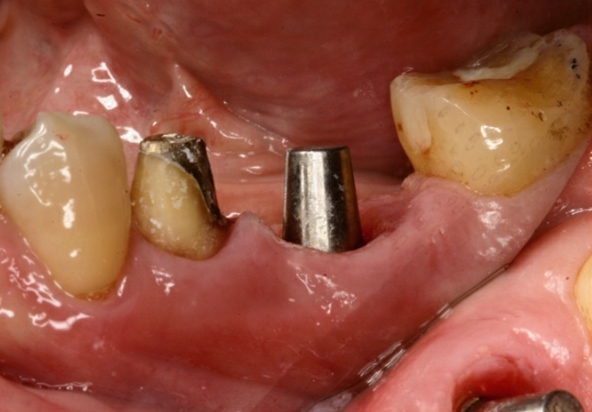

斷裂牙齒或是殘留牙根未有發炎反應的情況下,可以於當天立即拔牙立即植牙,不須再二次手術,大幅縮減等待裝牙時間並且讓手術傷口達到最小化。